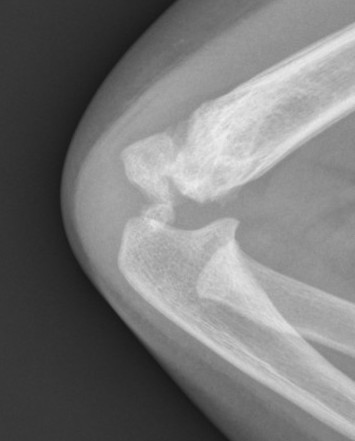

Xray

Distal physis not ossified < 1 year

- radius and ulna lose normal association with distal humerus

- posteromedial displacement of the ulnohumeral joint

- appears like an elbow dislocation

- disruption of radio-capitellar line